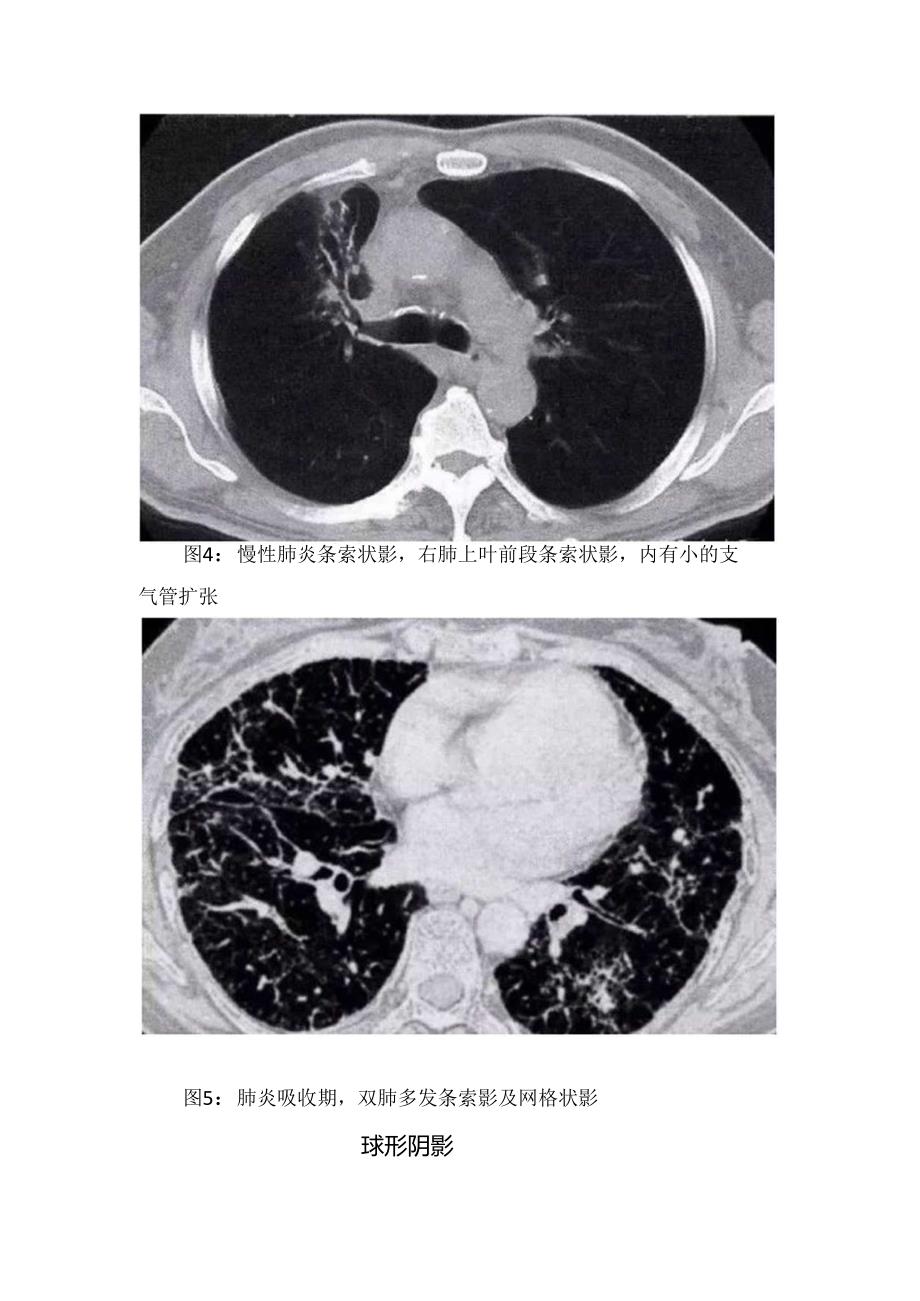

2、征,边缘常较淡,模糊(图3)。图3:肺炎大片状实变,左肺上叶大片状实变影,体积不缩小,其内有支气管空气征条索状及网状阴影此征常见于放射性肺炎,慢性肺炎,间质性肺炎和肺炎的吸收期。病变为增殖为主,也可合并有实质性肺泡炎。表现为斑片状不规则的条索状混合影。边缘可清楚,也可模糊(图4、图5)。图4:慢性肺炎条索状影,右肺上叶前段条索状影,内有小的支气管扩张图5:肺炎吸收期,双肺多发条索影及网格状影球形阴影见于金黄色葡萄球菌肺炎,真菌性肺炎,炎性假瘤。金黄色葡萄球菌肺炎,多发或单发的球形影,多为1.3cm边缘较清晰,密度较均匀,增强时为周围强化,但易变,且常合并空洞:真菌性肺炎是脓肿与肉芽肿,变化慢:炎性假痛,大小不一,边缘可光整,毛刺,增强可均匀或混合强化(图6、图7)。图7:球形肺炎,与图26为同一患者,经抗感染治疗后2周,病灶明显缩小空洞常见于化脓性肺炎或真菌性肺炎。见环形的透亮区,边缘可清晰,可模糊。壁可厚可薄。常伴有斑片状模糊影或小结节影(图8)。图8:右肺上叶脓肿伴空洞,脓肿空洞为厚壁,内壁不规则,周国有斑片状影,边缘模糊胸膜病变合并积液,后期胸膜局部增厚。